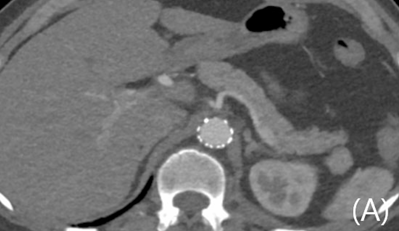

전산화단층촬영에서 자상으로 인해 대동맥에 거짓동맥류와 이와 관련한 광범위한 후복강 혈종이 보이고 있음 (Fig. 1A, B). 거짓동맥류가 생긴 위치는 복강동맥이 기시하는 높이의 뒤쪽 왼쪽인 5시 방향이었음. 이와 연관된 혈종은 후복강의 대동맥 주변과 횡격막 다리의 뒤쪽을 따라 연장되어 있었음. 그 외 다른 흉강이나 복강내 장기의 손상은 동반되지 않았음.

Fig 1A

Contrast-enhanced axial (A), coronal (B) CT scan demonstrates ruptured pseudoaneurysm (arrows) at posterior aspect of abdominal aorta causing redundant hemoretroperitoneum.

Fig 1B